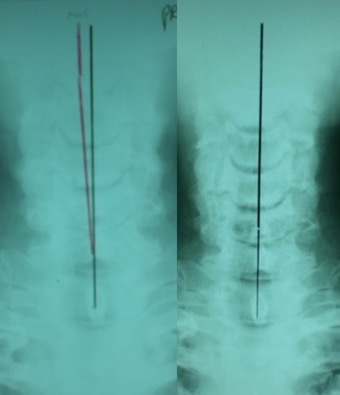

A full-spine radiographic assessment (Figures 2 and 3) was taken and analyzed using the Harrison posterior tangent method18,19 for the sagittal images and the modified Risser-Ferguson method19 for the coronal images. These methods are reliable and repeatable, as is posture.18–20 The images revealed a complete lack of cervical lordosis (absolute rotation angle from C2-C7=-1°; normal =34-42,21–23 forward head posture (FHP=35mm vs. <15mm normal22), and an atlas plane line (APL) of 10° (vs. 24-29 normal21,22) (Figure 3). The patient had well-demarcated osteoarthritic bone spurs from C4-C7 (Figure 3). On the posterior-anterior cervical radiograph, the patient had a left head translation of 7mm (vs. 0mm normal) (Figure 2).

After the initial 3-months (Figure 2), his left head translation was completely re-aligned to midline. His pain levels remained a 7/10 and still complained of right-sided facial pains. After another 3-months of sagittal cervical static extension-compression 2-way traction (Figure 5), his pain intensity dropped to 2.5/10, and he also reduced his Tegretol use to 100mg/day (vs. 800mg/day initially). His FHP reduced (24mm vs. 33mm), lordosis increased (-17° vs. -1°), and APL increased (-20° vs. -10°).

Following another 3-months of a more dynamic type of cervical extension 2-way traction (Figure 5), he regressed, having a resurgence of pain levels (4/10) corresponding with worsening postural radiographic parameters (FHP increased to 33mm; ARA increased to -10°; APL reduced to -17°). He also increased his medication to 400mg/day. He was encouraged by his family to quit treatment, but he chose to continue as long as he could re-commence the former static extension-compression 2-way traction that had achieved the initial symptom relief.

He was put back on the initial static extension-compression 2-way traction that had resulted in the initial symptomatic relief. After 3 further months of treatment (12-months overall), he again improved having an NRS of 2/10, reducing FHP to 26mm, increasing ARA to -14°, and increasing APL to 14°. He was for the first time able to stop taking Tegretol, and also reported no facial ‘shock-like, lightning-bolt’ pains. He also improved on 7/8 SF-36 QOL indices (Table 1). This finalized 1 year of ‘corrective care,’ where, moving forward, he continued on a maintenance care plan (1-2 treatments per month).

A 1-year follow-up assessment (2 years since initial presentation) demonstrated he had maintained wellness, having an NRS of 2/10 and a further slight improvement of lateral craniocervical radiographic parameters (21mm FHP, -18° ARA, -22° APL). He had improved on half of the SF-36 QOL indices, though showed lower scores for half the indices, including pain possibly due to a recent onset of acute low-back pain due to cutting wood and playing softball. Regarding his former complaint of TN, he said he felt ‘the best ever’ and chose to discontinue further care.